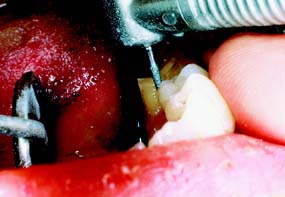

A metal matrix band around the adjacent tooth for protection may be helpful; however, the thin band can nonetheless be perforated and the underlying enamel damaged. The preferred method is to use the proximal enamel of the tooth that is being prepared for protection of the adjacent structures. Teeth are 1.5 to 2 mm wider at the contact area than at the cementoenamel junction. Therefore, a thin, tapered diamond can be passed through the interproximal contact area (Fig. 7-2) to leave a slight lip or fin of enamel without resulting in excessive tooth reduction or necessitating undesirable angulation of the rotary instrument. The latter situation, tipping the diamond unnecessarily away from the adjacent proximal surface, is a common clinical error.

Fig. 7-2 Damage to adjacent teeth is prevented by positioning the diamond so a thin lip of enamel is retained between the bur and the adjacent tooth. A, Note that the orientation of the diamond parallels the long axis of this premolar. B, Proximal reduction almost complete. Note that enamel was maintained mesial to the path of the diamond as the reduction progressed.